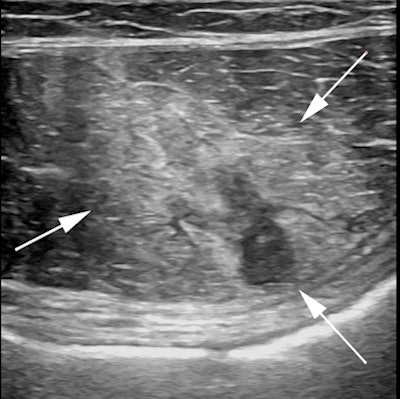

Professional tennis player who experienced acute onset abdominal wall pain while serving during a match. Transverse ultrasound image of the left rectus abdominus muscle demonstrates an acute muscle injury with edema, acute hemorrhage, and a small focal hyperacute hematoma.The pandemic and subsequent lockdown in March 2020 shut down sports imaging services in Spain for six weeks. Activity has resumed since then.